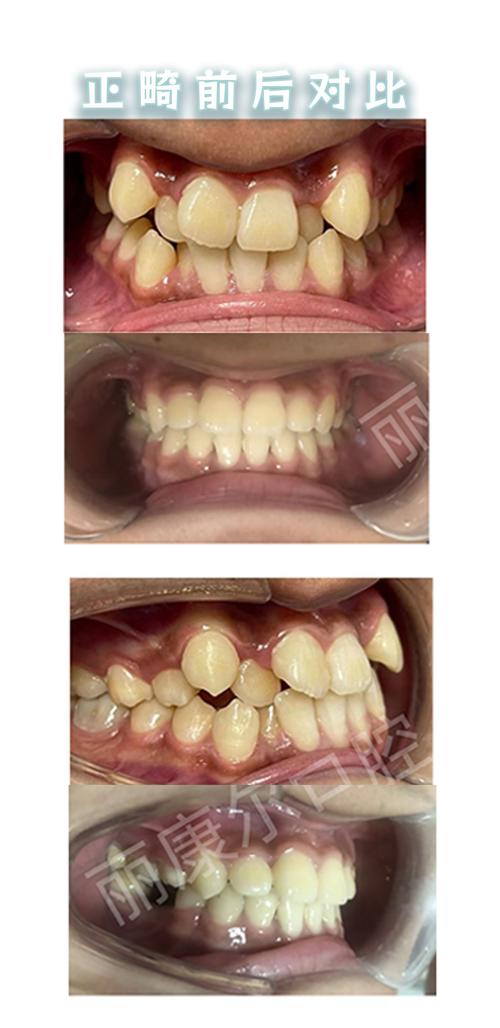

- 牙龈敏感与炎症:孕期激素变化使牙龈血管扩张、通透性增加,易引发妊娠期牙龈炎,表现为牙龈红肿、出血,若此时佩戴固定矫治器(如托槽、弓丝),食物嵌塞和口腔清洁难度增加,可能加重牙龈炎症。

- 暂停正畸加力:孕期不建议进行牙齿主动移动(如调整弓丝、更换橡皮筋),以免因激素影响导致牙根吸收或骨损伤,若已佩戴矫治器,需加强口腔清洁,避免牙龈炎。